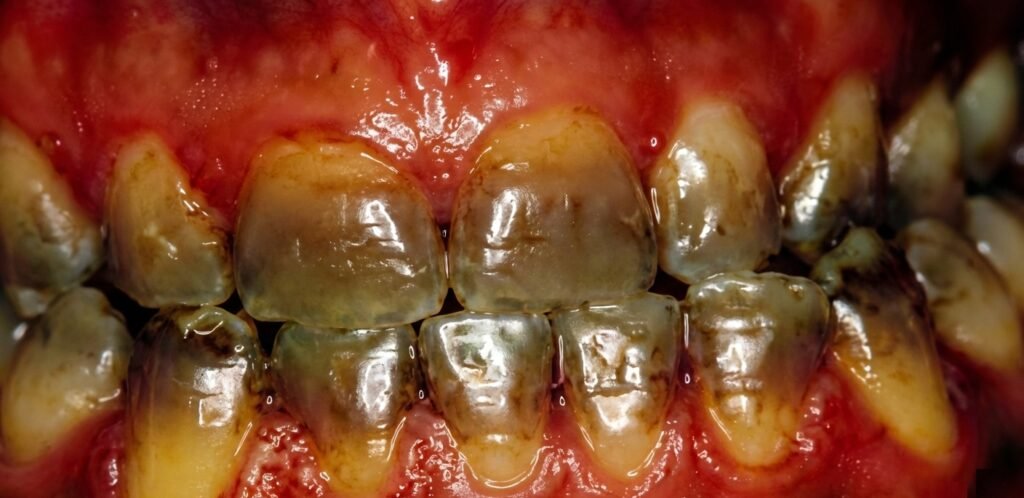

- Mélanodontie infantile de Beltrami-Romieu : Altération de l’émail de la dent temporaire qui se voit chez l’enfant à partir de douze mois. Il s’agit d’une dysplasie (anomalie de la formation) de l’émail qui est héréditaire. Elle se traduit par la disparition de l’émail (il se dissout ou se détache par plaques). Dès lors, les dents ne sont plus protégées et entament un processus de destruction. Les premières dents atteintes (parfois les seules) sont les incisives supérieures. De petites plaques d’émail se détachent, elles deviennent progressivement noires, puis se détruisent pour ne laisser que des chicots.

Ce type de lésions doit être différencié de la mélanodontie infantile de Beltrami qui s’observe aussi au niveau des dents temporaires. Elle se caractérise par :

- L’apparition de taches brunâtres sur la face vestibulaire des incisives maxillaires qui vont s’étendre en profondeur en détruisant progressivement la couronne dentaire ;

- Une coloration noire des moignons dentinaires.

Ces lésions atteignent l’ensemble des dents temporaires (à l’exception des incisives mandibulaires).